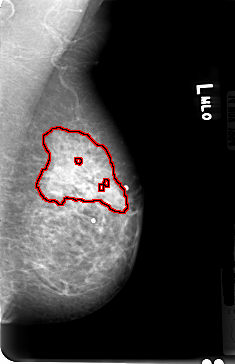

FILE: B_3030_1.LEFT_MLO.OVERLAY

TOTAL_ABNORMALITIES 1

ABNORMALITY 1

LESION_TYPE CALCIFICATION TYPE PUNCTATE DISTRIBUTION SEGMENTAL

ASSESSMENT 4

SUBTLETY 2

PATHOLOGY MALIGNANT

TOTAL_OUTLINES 4

BOUNDARY

CORE